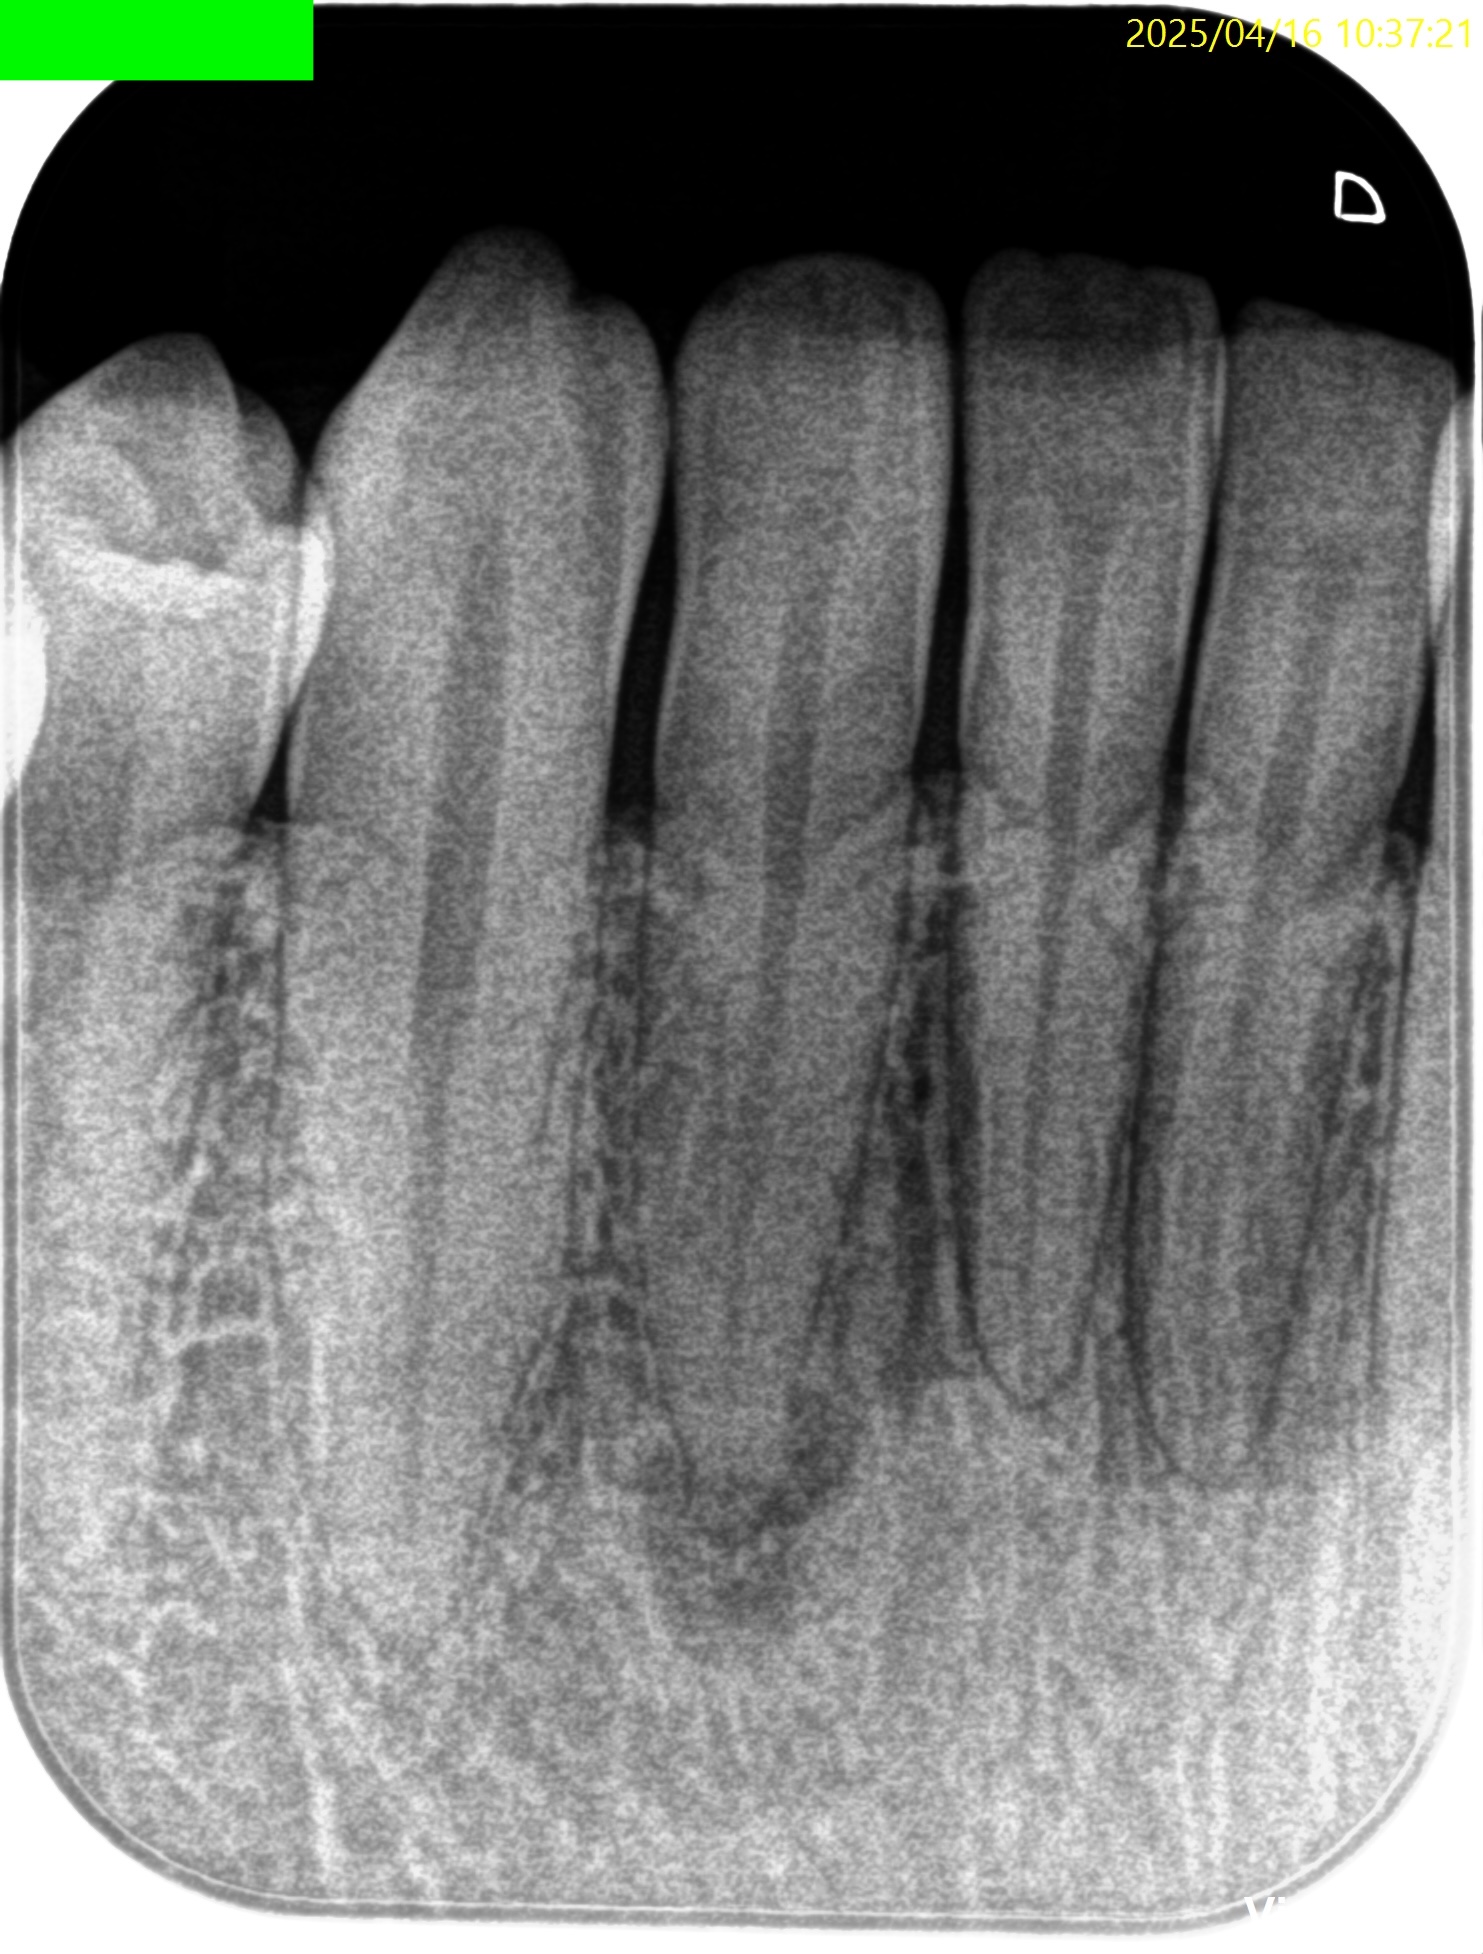

PA(2025.4.16)

CBCT(2025.4.16)

切端から3.5mmの部分を1.7mm削合すると露髄し、根管治療を行うための根管に到達できるだろう。

Pre-op Endo Diagnosis(2025.4.16)

Pulp Dx: Normal Pulp Tissues

Periapical Dx: Symptomatic apical periodontitis

Recommended Tx: RCT